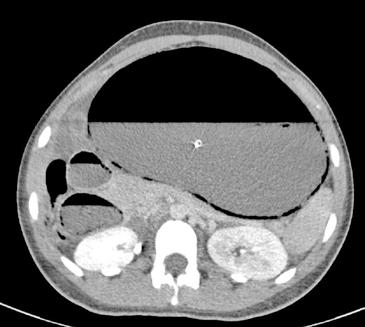

Paciente varón de 6 años sin antecedentes de interés, que acudió al Ser vicio de Urgencias 5 horas (h) después de sufrir un trauma contuso en hipogastrio con el manillar de la bicicleta. El paciente presentaba buen estado general y constantes vitales normales pero refería dolor abdominal genera lizado y continuo, sin otros síntomas acompañantes. En la inspección abdo minal se observó una lesión eritematosa-equimótica de aproximadamente 3x3 cm en hipogastrio, levemente dolorosa pero sin alteraciones subyacen tes (Figura 1). El abdomen era blando, depresible y doloroso a la palpación profunda pero sin defensa ni signos de irritación peritoneal. En la analítica sanguínea (AS) se documentó una hemoglobina de 13.5 g/dL, sin elevación de enzimas hepáticas ni pancreáticas, el uroanálisis también fue normal. Se realizó una ecografía de abdomen en la que se visualizaban pequeñas lengüetas de líquido libre intraabdominal y focos de hiperecogenicidad de la grasa mesentérica con engrosamiento focal del peritoneo. Se completó el estudio con una tomografía axial computarizada (TAC) abdominopélvica con contraste que identificó escasa cantidad de líquido libre perihepático e interasas con leve distensión de asas ileales, sin observar otras lesiones. Todo lo anterior sugestivo de contusión mesentérica por lo que se decidió

Debido al empeoramiento clínico se solicitó una ecografía de abdomen durante la cual estuvo presente el equipo tratante y en la que se evidenció aumento del líquido libre de aspecto ecogénico sin otras alteraciones. Sin embargo, ante la evolución tórpida y la localización de la contusión abdo minal se comunicó al radiólogo la posibilidad de una perforación intestinal, quien realizó una segunda exploración ecográfica enfocada en las zonas cefálicas y anteriores del abdomen en las que se ubicaría el aire, entonces se visualizaron artefactos en la superficie hepática que sugerían burbujas aéreasextraluminales (Figura 2A). Se realizó una radiografía toracoabdomi nal (RxTA) que confirmó la presencia de neumoperitoneo subdiafragmático bilateral (Figura 2B).

Figura 1. Lesión eritematosa-equimótica en hipogastrio producida por manillar de bicicleta (cabeza de flecha).

Figura 2. Ecografía con burbujas aéreas extraluminales en la superficie hepática sugestivas de neumoperitoneo (A, flechas). RxTA con neumoperitoneo subdiafragmático bilateral (B, flechas).